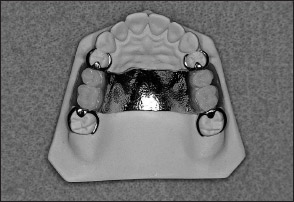

Traditionally, fixed partial dentures have been attached to abutments using dental cements, while removable partial dentures have been attached to abutments by other means. In removable partial denture prosthodontics, there are two principle types of retainers. They are termed extracoronal retainers and intracoronal retainers. Extracoronal retainers consist of two fingers of metal (ie, clasps) that lie on the surface of a clinical crown (Fig 1-3). One finger of metal is termed a retentive clasp, while the other is termed a reciprocal clasp. The retentive clasp is located in an undercut area of the clinical crown and resists displacement of the prosthesis away from the underlying hard and soft tissues. The reciprocal clasp is located in a non-undercut area and serves as a bracing or stabilizing element for the prosthesis. The resultant assembly is termed an extracoronal retainer because the retentive and reciprocal components lie on the external surfaces of an abutment.

Unlike extracoronal retainers, intracoronal retainers are contained entirely within the contours of a clinical crown (Fig 1-4). Consequently, the use of intracoronal retainers generally requires the fabrication of two or more specially designed, complete-coverage crowns. In most instances, retention of intracoronal removable partial dentures is dependent upon exact parallelism of the retentive assemblies. Each assembly consists of two parts, commonly termed matrix (“female”) and patrix (“male”). Figure 1-5 illustrates the joining of a patrix and matrix to form a functional retentive unit. When a dislodging force is applied to the removable partial denture, binding occurs between the external walls of the patrix and the internal walls of the matrix. This binding results in retention of the prosthesis.